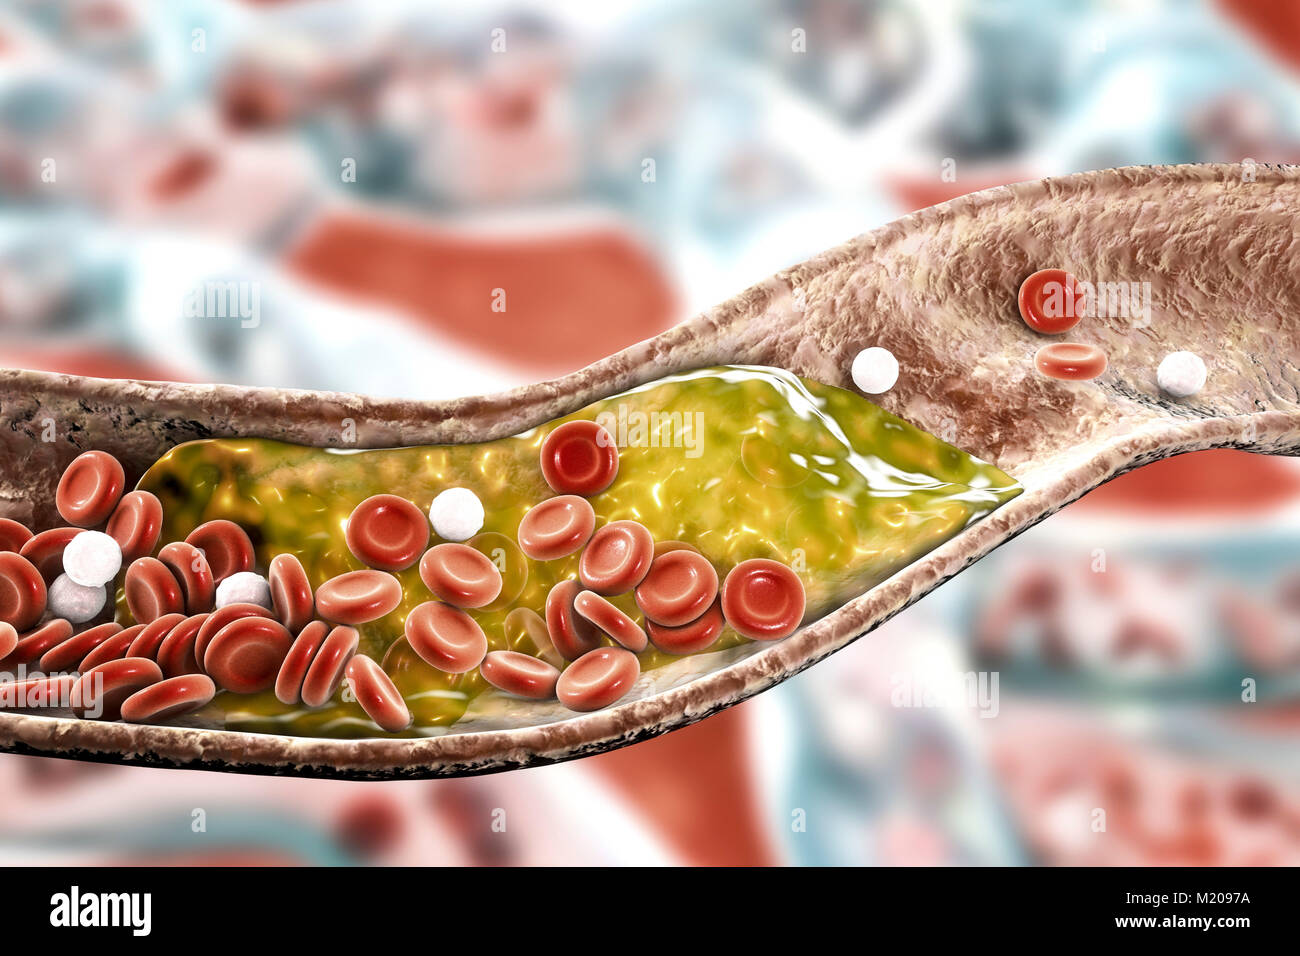

Atheromatous plaque inside blood vessel, computer illustration. A cholesterol atheroma is causing a narrowing of an artery (atherosclerosis). Stock Photohttps://www.alamy.com/image-license-details/?v=1https://www.alamy.com/stock-photo-atheromatous-plaque-inside-blood-vessel-computer-illustration-a-cholesterol-173340254.html

Atheromatous plaque inside blood vessel, computer illustration. A cholesterol atheroma is causing a narrowing of an artery (atherosclerosis). Stock Photohttps://www.alamy.com/image-license-details/?v=1https://www.alamy.com/stock-photo-atheromatous-plaque-inside-blood-vessel-computer-illustration-a-cholesterol-173340254.htmlRFM2097A–Atheromatous plaque inside blood vessel, computer illustration. A cholesterol atheroma is causing a narrowing of an artery (atherosclerosis).

Atheromatous plaque inside blood vessel, computer illustration. A cholesterol atheroma is causing a narrowing of an artery (atherosclerosis). Stock Photohttps://www.alamy.com/image-license-details/?v=1https://www.alamy.com/stock-photo-atheromatous-plaque-inside-blood-vessel-computer-illustration-a-cholesterol-173340259.html

Atheromatous plaque inside blood vessel, computer illustration. A cholesterol atheroma is causing a narrowing of an artery (atherosclerosis). Stock Photohttps://www.alamy.com/image-license-details/?v=1https://www.alamy.com/stock-photo-atheromatous-plaque-inside-blood-vessel-computer-illustration-a-cholesterol-173340259.htmlRFM2097F–Atheromatous plaque inside blood vessel, computer illustration. A cholesterol atheroma is causing a narrowing of an artery (atherosclerosis).

Atheromatous plaque inside blood vessel, computer illustration. A cholesterol atheroma is causing a narrowing of an artery (atherosclerosis). Stock Photohttps://www.alamy.com/image-license-details/?v=1https://www.alamy.com/stock-photo-atheromatous-plaque-inside-blood-vessel-computer-illustration-a-cholesterol-173340260.html

Atheromatous plaque inside blood vessel, computer illustration. A cholesterol atheroma is causing a narrowing of an artery (atherosclerosis). Stock Photohttps://www.alamy.com/image-license-details/?v=1https://www.alamy.com/stock-photo-atheromatous-plaque-inside-blood-vessel-computer-illustration-a-cholesterol-173340260.htmlRFM2097G–Atheromatous plaque inside blood vessel, computer illustration. A cholesterol atheroma is causing a narrowing of an artery (atherosclerosis).

Atheromatous plaque inside blood vessel, computer illustration. A cholesterol atheroma is causing a narrowing of an artery (atherosclerosis). Stock Photohttps://www.alamy.com/image-license-details/?v=1https://www.alamy.com/stock-photo-atheromatous-plaque-inside-blood-vessel-computer-illustration-a-cholesterol-173340258.html

Atheromatous plaque inside blood vessel, computer illustration. A cholesterol atheroma is causing a narrowing of an artery (atherosclerosis). Stock Photohttps://www.alamy.com/image-license-details/?v=1https://www.alamy.com/stock-photo-atheromatous-plaque-inside-blood-vessel-computer-illustration-a-cholesterol-173340258.htmlRFM2097E–Atheromatous plaque inside blood vessel, computer illustration. A cholesterol atheroma is causing a narrowing of an artery (atherosclerosis).

Atheromatous plaque inside blood vessel, computer illustration. A cholesterol atheroma is causing a narrowing of an artery (atherosclerosis). Stock Photohttps://www.alamy.com/image-license-details/?v=1https://www.alamy.com/stock-photo-atheromatous-plaque-inside-blood-vessel-computer-illustration-a-cholesterol-173340255.html

Atheromatous plaque inside blood vessel, computer illustration. A cholesterol atheroma is causing a narrowing of an artery (atherosclerosis). Stock Photohttps://www.alamy.com/image-license-details/?v=1https://www.alamy.com/stock-photo-atheromatous-plaque-inside-blood-vessel-computer-illustration-a-cholesterol-173340255.htmlRFM2097B–Atheromatous plaque inside blood vessel, computer illustration. A cholesterol atheroma is causing a narrowing of an artery (atherosclerosis).